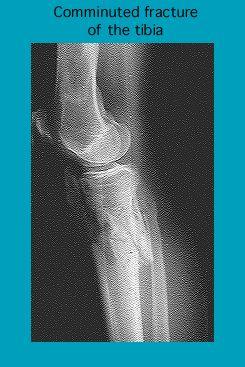

Radiograph of a comminuted fracture of the tibia